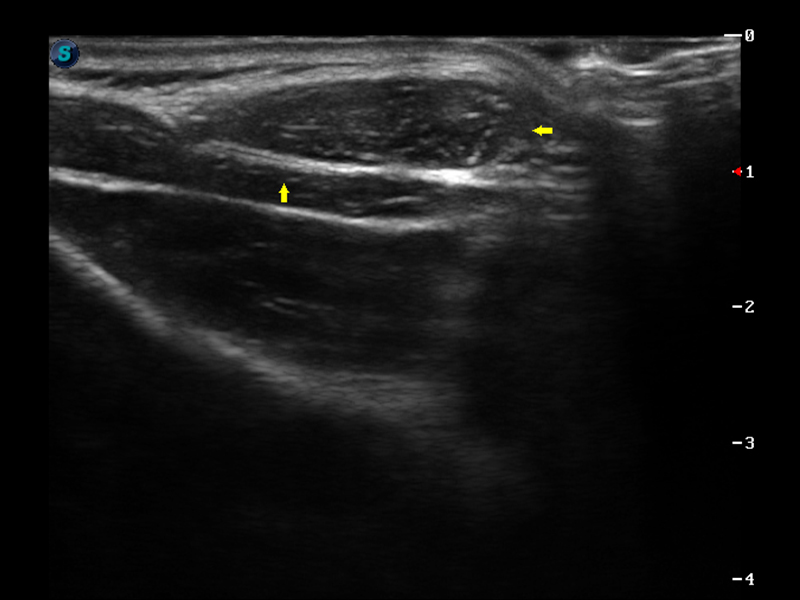

S9便携式彩色多普勒超声诊断仪是新葡的京集团8814检测站研发的高端便携彩超设备,外观设计新颖、产品性能卓越。S9在便携超声领域采用了突破传统的触摸屏交互设计,并以先进的软件硬件技术和设计理念,为您带来清晰的图像质量、稳定的工作性能和便捷的操作体验。